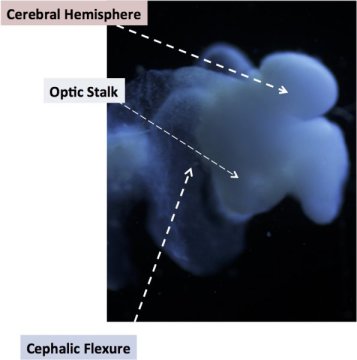

Bu videoda kök hücrelerinden 96 saatte bir beyin oluşuyor. Harikulade.

Son yıllarda kök hücre teknolojisindeki ilerlemeler çığır açıcı nitelikte. Kaliforniya üniversitesi tarafından hazırlanan bu videoda farelerin kök hücreleri ile yapılan bir deney var. Videonun başında göreceğiniz kök hücre kümelerinin her bir tanesinin içerisinde 10 kadar hücre var ayrıca bu hücreler genetik olarak değiştirilip ışığa duyarlı hale getirilmiş. Bu hücreler bir süre sonra ışıkla harekete geçmeye

Ohio Devlet Üniversitesindeki bilim adamları bir tabakta bir insan beynini, cilt hücrelerinden oluşturmayı başardılar. Bu beyin 5 aylık bir fetüsün olgunluğuna sahip.

Bu beyin organımsısı yetişkin insan cilt hücrelerinden dönüştürülmüş ve şu ana kadar oluşturulabilen en tam beyin modeli Ohio Devlet Üniversitesi’nde biyolojik kimya profösörü olan Rene Anand’a göre. Laboratuvarda üretilen beyin bir kalem silgisi büyüklüğünde, ve bebek beyninde bulunan gen ve yapıların yüzde 99’unu içerisinde barındırıyor. Böyle bir sistem hem etik hem de hızlı bir şekilde